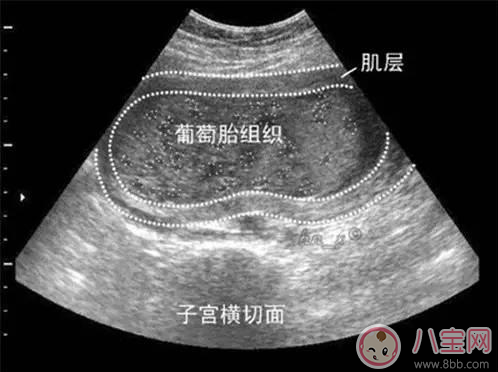

葡萄胎是由于絨毛膜滋養(yǎng)層細(xì)胞異常增生,絨毛發(fā)生水腫變形,呈無數(shù)個水泡相互連接,形似成串的葡萄,故名曰葡萄胎,又被稱為“水泡樣胎塊”?;加衅咸烟ヒ坏┐_診后要刮宮處理。如果子宮不大,內(nèi)容物比較少,那么一次就可以刮干凈,對女性子宮的傷害也較小,但是如果內(nèi)容物比較多,有數(shù)不清的水泡,會轉(zhuǎn)移,一次很難刮干凈,那么需要兩次刮宮。